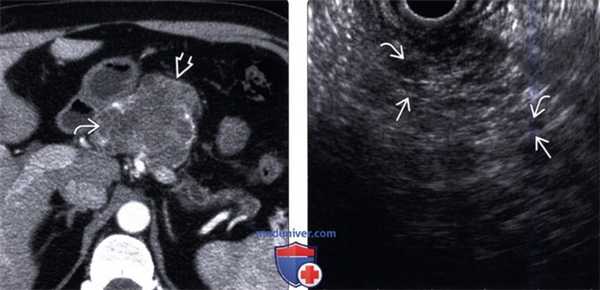

(Левый) При КТ с контрастным усилением на аксиальной томограмме определяется четко отграниченное дольчатое образование поджелудочной железы, содержащее скопления мелких кист, что создает характерную для серозной цистаденомы картину пчелиных сот.

(Правый) У этого же пациента при эндоскопическом ультразвуковом исследовании визуализируется преимущественно эхогенное объемное образование; такая картина обусловлена наложением многочисленных акустических сигналов от бессчетного количества мелких кист и разделяющей их фиброзной стромы. После хирургической резекции подтвержден диагноз серозной цистаденомы поджелудочной железы.